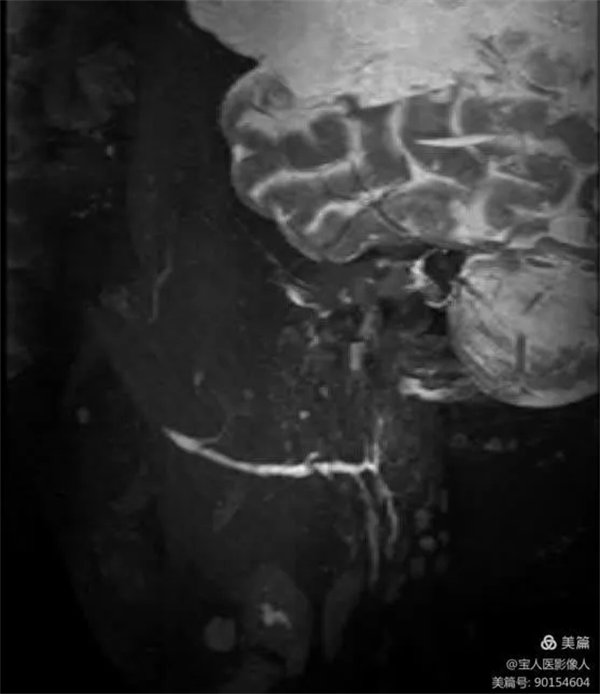

患者磁共振檢查,可清晰地顯示正常腮腺導管主干和大分支導管。

圖2,左側腮腺主導管及分支